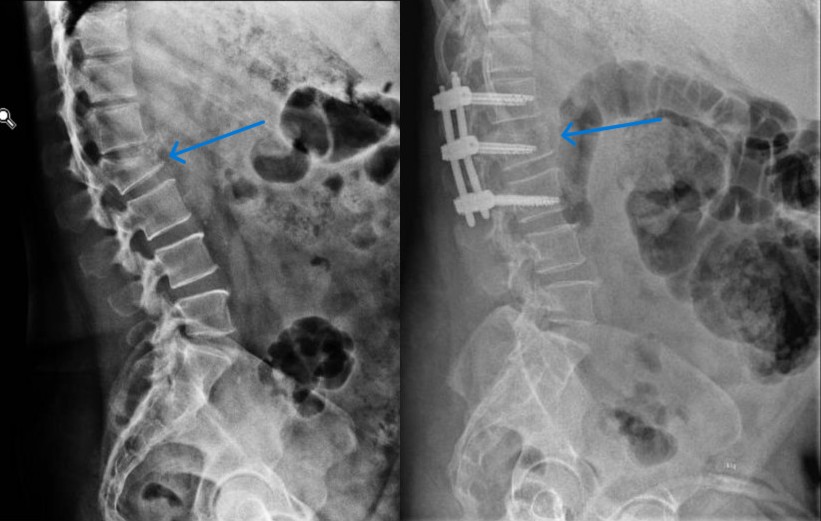

–Fracturas vertebrales: Frecuentes sobre todo en la columna dorso-lumbar, pueden aparecer como consecuencia de mecanismos muy diversos; desde grandes traumatismos, en cuyo caso su tratamiento puede estar condicionado por la presencia de otras lesiones, o bien tras traumatismos banales o incluso de forma espontánea, sin traumatismo alguno. Estos últimos casos definen las «fracturas patológicas» en las que es preciso buscar una causa subyacente estructural o sistémica que haya provocado el debilitamiento óseo. Esta situación es especialmente frecuente en mujeres tras la menopausia debido al desarrollo de osteoporosis. Estos casos precisan iniciar un tratamiento para compensar la desmineralizacón ósea. El tratamiento de las fracturas depende fundamentalmente del grado de deformidad asociado, la afectación de ligamentos (ambos aspectos definen la presencia o no de inestabilidad) y el que exista o no una lesión neurológica. En caso de fracturas estables sin déficit neurológico se emplea una ortesis mientras que en presencia de inestabilidad o afectación neurológica debe valorarse la cirugía.

- Estabilizacion vertebral percutánea: Es el procedimiento empleado para tratar los casos que precisan fijar dos o más vértebras debido a la presencia de inestabilidad o fracturas. Gracias al empleo de imagen intraoperatoria y a los sistemas de fijación de alta precisión es posible llevar a cabo esta técnica de forma mínimanente invasiva mediante pequeñas incisiones de apenas 2 cm a través de las cuales se introducen tornillos al pedículo de la vértebra así como barras laterales. El respeto por la musculatura paraespinal, clave para el resultado final, es por tanto máximo gracias a esta técnica. La ejecución de la misma gracias al aprovechamiento de aspectos como la colocación bicortical de los implantes y las técnicas de reduccion percutánea de la deformidad permiten un restablecimiento de la anatomía en una amplia proporción de casos con un riesgo mínimo.